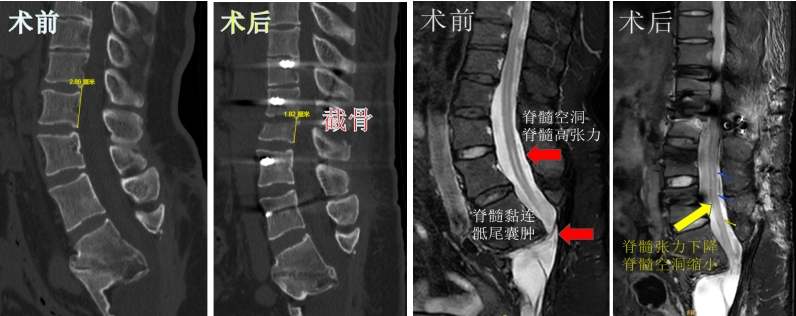

患者术后疼痛和感觉障碍有所改善,术后10天复查核磁可见脊髓张力下降、脊髓空洞缩小,复查CT可见椎体缩短了10mm左右,达到了本次治疗目的。总之,对于成人复发的脊髓拴系,椎体缩短截骨术为治疗提供了一个新的手术选择。

孙振兴及团队考虑到再次松解脊髓和神经黏连,虽然可以直接松解黏连,但面临脑脊液漏、感染和神经损伤的高风险,且脊髓高张力和脊髓空洞难以缓解。因患者的症状与脊髓高张力和空洞有关,而椎体缩短截骨术,可直接降低脊髓高张力,也可避免因松解手术导致的脑脊液漏和神经损伤,但此术会缩短患者身高且手术难度大、手术技术要求高。团队经过综合评估以及跟患者及家属的充分沟通,最终决定选择椎体缩短截骨术为患者进行治疗。